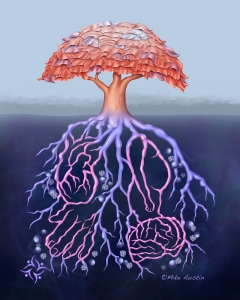

Welcome to my Patient and Professional Marketing page, where I harness the power of anatomical illustrations to educate and empower both patients and medical professionals. My unique approach combines artistry and education to convey complex surgical procedures and the utilization of medical devices in an easily understandable manner.